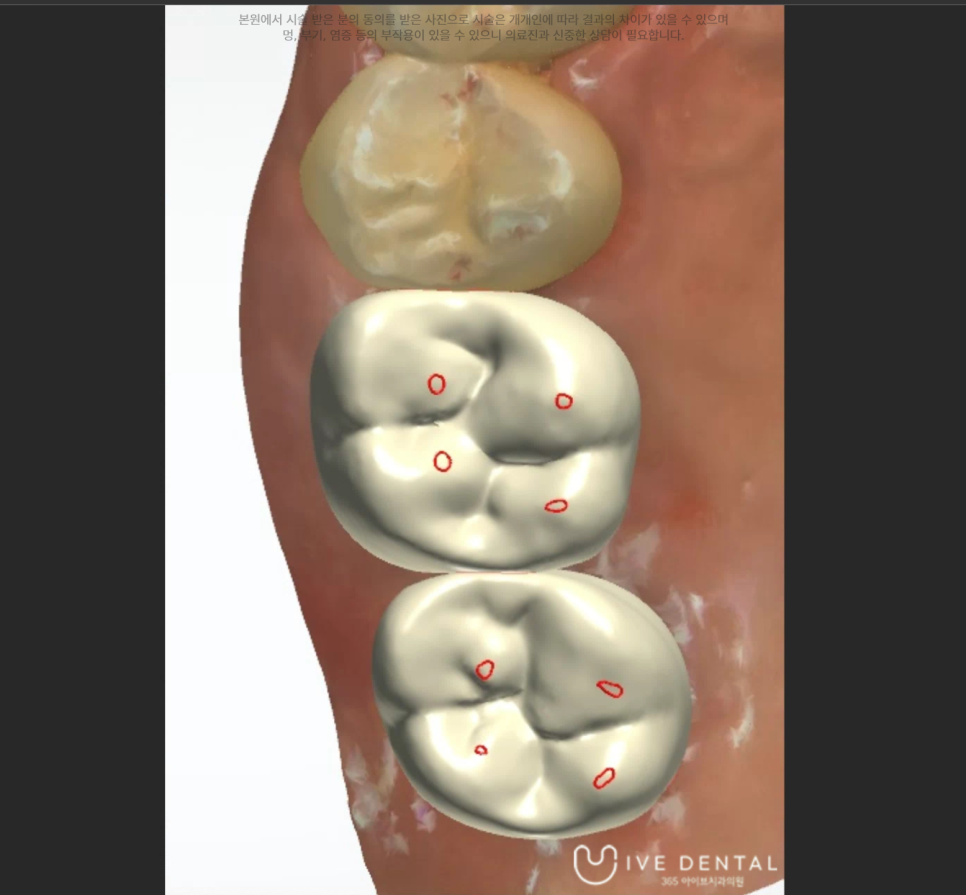

아이브치과에서는 완전 디지털화 시스템으로 보철물 디자인부터 제작까지 원내 기공소에서 실시하고 있습니다.

또한 디자인의 경우에 외부 기공사에게 맡기지 않고 원장인 제가 직접 디자인하고 있습니다.

따라서 훨씬 고 퀄리티의 기공 물을 만들 수 있고 수정이 필요하거나 한 경우에도 빠르게 즉각적으로 대응이 가능합니다.

환자분의 구강 구조에 맞춰 보철물을 제작하고요.

다른 자연치와 이질감이 없어야 하므로 색깔도 세밀하게 맞추어 제작을 진행합니다.